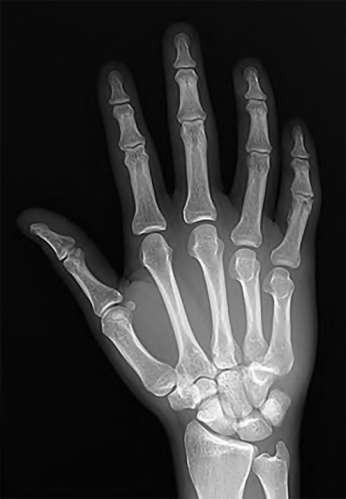

A 35-year-old woman reports wrist pain after a fall onto an outstretched hand. On exam, she has focal tenderness over the wrist snuffbox. A radiograph and CT image are shown in Figures A and B. What is the proper treatment of her injury?